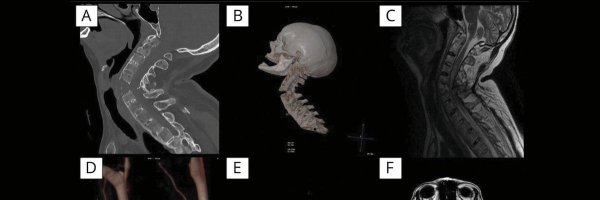

C'est pas le boulot des radiologues ça? @ZeClint ?

Un irm corps entier annuel? Wtf

My annual MRI scan gives me a USB stick with the data, but you need this commercial windows software to open it. Ran Claude on the stick and asked it to make me a html based viewer tool. This looks... way better.